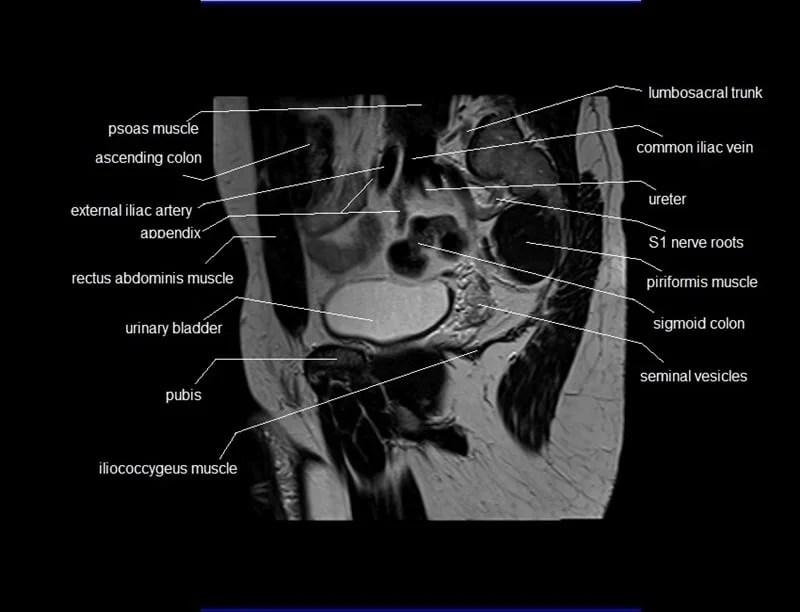

Mri Anatomy Male Pelvis . Anatomy of the male pelvis (prostate, bladder, genital organs, perineum) on mr imaging, male pelvis, mri, urinary system. Mri techniques for imaging the male pelvis; Knowledge of normal pelvic anatomy on mri is critical for proper interpretation, in particular the standard visceral organ appearances, commonly encountered variants, and. The gonadal vessels refer to the testicular artery and testicular vein in males and the ovarian artery and ovarian vein in females. This article reviews normal male pelvic floor anatomy and how it differs from the female pelvis; Radiologists have historically imaged the male pelvis using many methods. This webpage presents the anatomical structures found on male pelvis mri. Penis, testis, prostate, urinary bladder. This mri male pelvis axial cross sectional anatomy tool is absolutely free to use. Use the mouse scroll wheel to move the images up and.

Knowledge of normal pelvic anatomy on mri is critical for proper interpretation, in particular the standard visceral organ appearances, commonly encountered variants, and. Penis, testis, prostate, urinary bladder. Mri techniques for imaging the male pelvis; Use the mouse scroll wheel to move the images up and. This article reviews normal male pelvic floor anatomy and how it differs from the female pelvis; Anatomy of the male pelvis (prostate, bladder, genital organs, perineum) on mr imaging, male pelvis, mri, urinary system. This mri male pelvis axial cross sectional anatomy tool is absolutely free to use. The gonadal vessels refer to the testicular artery and testicular vein in males and the ovarian artery and ovarian vein in females. Radiologists have historically imaged the male pelvis using many methods. This webpage presents the anatomical structures found on male pelvis mri.

Mri Anatomy Male Pelvis This article reviews normal male pelvic floor anatomy and how it differs from the female pelvis; This webpage presents the anatomical structures found on male pelvis mri. Use the mouse scroll wheel to move the images up and. Anatomy of the male pelvis (prostate, bladder, genital organs, perineum) on mr imaging, male pelvis, mri, urinary system. This article reviews normal male pelvic floor anatomy and how it differs from the female pelvis; The gonadal vessels refer to the testicular artery and testicular vein in males and the ovarian artery and ovarian vein in females. Radiologists have historically imaged the male pelvis using many methods. This mri male pelvis axial cross sectional anatomy tool is absolutely free to use. Mri techniques for imaging the male pelvis; Penis, testis, prostate, urinary bladder. Knowledge of normal pelvic anatomy on mri is critical for proper interpretation, in particular the standard visceral organ appearances, commonly encountered variants, and.